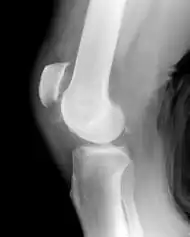

Patellar tendon rupture showing a marked distance between the tibial tuberosity and the bottom of the knee cap.

Patellar tendon rupture

Patellar tendon rupture can usually be diagnosed by physical examination. The most common signs are: tenderness, the tendon's loss of tone, loss of ability to raise the straight leg and observation of the high-riding patella. Radiographically, patella alta can be detected using the Insall and Salvati method when the patella is shorter than its tendon. Partial tears may be visualized using MRI scans.[4]